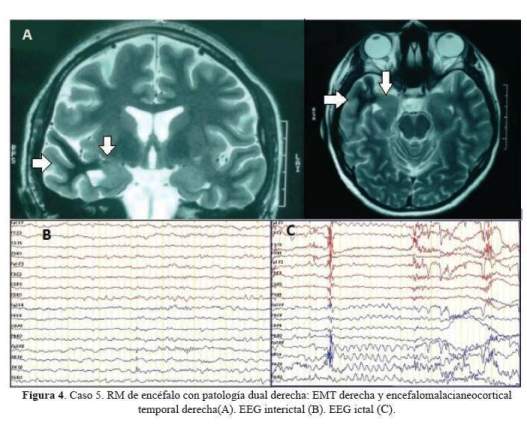

De los 5 casos, 3 cirugías correspondieron a pacientes con epilepsia temporal mesial derecha (2 por esclerosis mesial temporal y 1 por ganglioglioma mediobasal temporal anterior) y 2 correspondieron a patología dual (1 con EMT derecha más lesión gliótica cicatrizal de un angioma cavernoso temporal neocorical ipsilateral operado previamente y 1 con EMT izquierda más gliosis frontal ipsilateral). De los 3 pacientes con epilepsia temporal mesial derecha, 2 sólo requirieron de estudios paraclínicos en fase 1: EEG/VideoEEG y RM encéfalo estructural y 1 requirió además de PET interictal (fase 2), pues a pesar de que la semiología y actividad electrográfica ictal correspondían a una epilepsia del lóbulo temporal mesial derecho, la RM de encéfalo dejaba duda respecto a si además de tener EMT derecha,tenía también EMT izquierda. A estos tres pacientes se les realizó lobectomía temporal anteromesial (LTA) que incluyó amigdalohipocampectomía, siguiendo las técnicas quirúrgicas del Programa de Epilepsia del London Health Sciences Centre, University of Western Ontario, Canadá (20). Las 2 pacientes con patología dual fueron intervenidas con el apoyo de electrocorticografía (ECoG) aguda o intraoperatoria. En una de ellas se demostró que la lesión frontal izquierda ipsilateral era silente, no se resecó y se realizó solo LTA izquierda. En la otra paciente, la ECoG orientó a realizar una lesionectomía ampliada de la lesión neocortical temporal anterior; pero tuvimos que abstenernos de realizar una amgdalohipocampectomía a pesar de tratarse de una patología dual, pues su reserva cognitiva y la memoria, tanto verbal como visual estaban indemnes. Es importante señalar que en ésta paciente la semiología ictal inicial era neocortical (auras auditivas, seguidas solo después de segundos de miedo). En la primera paciente con patología dual además se realizó estimulación cortical directa para la evaluación intraoperatoria del lenguaje con la paciente despierta; se puede revisar en detalle el procedimiento en un reporte del caso publicado previamente (21). No se realizaron en esta serie resecciones extratemporales. Los resultados de anatomopatología evidenciaron como etiología definitiva: 3 EMT, 1 ganglioglioma y 1 gliosis reactiva; esta última corresponde a la paciente con patología dual con lesión gliótica cicatrizal neocortical temporal derecha, operada en años previos de angioma cavernoso en dicha zona. Las imágenes de RM de encéfalo y EEG de los casos 1, 2, 3 y 5 pueden ser revisadas en la figura 1,figura 2,figura 3 y figura 4 Las imágenes del caso 4 pueden ser revisadas en un reporte de caso publicado previamente (21).

En el 2012, otro estudio randomizado y controlado realizado en 16 centros de Estados Unidos de Norteamérica (EEUU) comparó la lobectomía temporal anteromesial en ELT refractaria frente al tratamiento farmacológico, pero a diferencia del estudio canadiense las cirugías se realizaron precozmente, dentro de los 2 años de la presentación de crisis discapacitantes y el seguimiento fue por 2 años. Este estudio encontró una eficacia de libertad de crisis de 73% para cirugía frente a 0% para la continuación del tratamiento farmacológico (22). Ya en 1995, Thadini et al., reportaron un estudio, en el que seleccionaron en forma no randomizada pacientes con epilepsia del lóbulo temporal en quienes la semiología, los hallazgos electrográficos y las neuroimágenes fueron congruentes respecto al foco epileptógeno y encontraron una eficacia de libertad de crisis de 82%, correspondiendo el 90% de los casos a EMT como etiología y en ningún caso se requirió de estudios invasivos de monitoreo prolongado con electrodos intracraneales; hallazgos concordantes a los de nuestra serie (23). La eficacia para cirugía resectiva de epilepsia extratemporal ha sido reportadas en estudios no controlados, es menor que la obtenida en la cirugía temporal y fluctúa entre 34 a 66%, dependiendo de si la epilepsia en no lesional o si lo es (24).El caso 5 de nuestra serie, en el que se realizó solo lesionectomía neocortical temporal, a pesar de tener patología dual; requerirá de un seguimiento más prolongado, pues como reporta la literatura, el no resecar la EMT en estos casos establece una alta probabilidad de recurrencia de crisis (21). Sin embargo, la decisión estuvo justificada porque la paciente tenía indemne la memoria verbal y no verbal y las auras iniciaban con sintomatología neocortical temporal.